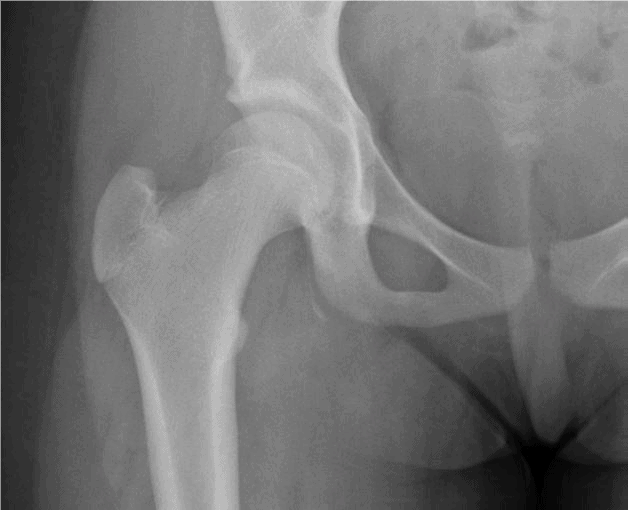

The patient is a 48-year-old woman who has had hip pain since joining her two sons and husband in a backyard touch football game yesterday afternoon. In particular, she describes planting her foot and trying so duck her older son’s grasp. She reports it is especially uncomfortable when driving or sitting at her desk at work.

View the images taken and consider what your next steps and a possible diagnosis would be.